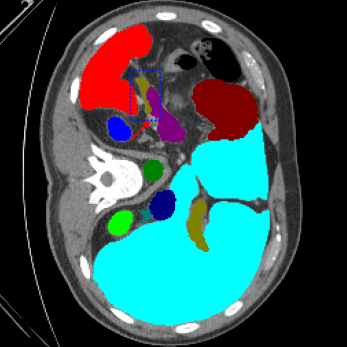

| Ground Truth | LoGoNet | DiNTS Search |

|---|---|---|

![]() |

We begin by qualitatively inspecting our model. Figure 3 compares the output of LoGoNet to the best performing baseline model in BTCV dataset, i.e., DiNTS Search (more qualitative comparisons can be found in appendix section 11). We see that our model particularly excels in segmenting organ boundaries. This can be attributed to our effective strategy for extracting local-range dependencies, which plays a crucial role in extracting details from input data. Our model’s adeptness in capturing long-range dependencies allows it to grasp contextual information that extends over significant distances within the data. Simultaneously, its proficiency in handling short-range dependencies ensures precision in capturing localized patterns.